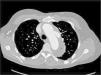

De acuerdo con la clasificación de Stanford, en nuestro estudio observamos que 17 pacientes (53.1%) fueron catalogados como StanfordA (fig. 4), mientras que los restantes 15 pacientes (46.9%) fueron catalogados como StanfordB (fig. 5). De acuerdo con la literatura, el subtipo StanfordA ocurre en el 60-70% de los casos6. En cuanto a la clasificación de De Bakey, el subtipo3 fue el más frecuentemente diagnosticado, con 15 pacientes (46.9%), seguido del subtipo1, que fue diagnosticado en 10 pacientes (31.2%), y del subtipo2 en 7 pacientes (21.9%).

Caso de disección aórtica StanfordA/De Bakey1. Paciente masculino de 53 años de edad con disección aórtica Stanford tipoA/De Bakey tipo1. La flecha blanca indica el colgajo de disección a nivel de la aorta ascendente, y la flecha negra el colgajo de disección a nivel de aorta descendente que se extiende hasta el segmento abdominal.